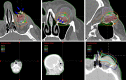

Sebaceous carcinoma is characterized by its aggressive local tumor behavior and ability to metastasize. Small periocular sebaceous carcinoma are typically treated by excision with cryotherapy. Larger tumors often require adjuvant external beam radiotherapy (EBRT) and/or exenteration surgery. When used alone, EBRT techniques typically exceed the tolerance of critical normal ocular structures. The interstitial orbital brachytherapy-boost technique permits dose escalation to the tumor bed, while minimizing radiation dose to critical normal ocular structures. Here, we present a case of orbital sebaceous carcinoma treated with excision, cryotherapy, and super-thick amniotic membrane fornix reconstruction. Then, after 3 weeks of healing, adjuvant-combined electron interstitial high-dose rate brachytherapy-boost was added to electron-beam radiotherapy to optimize the orbital radiation dose distribution, increase dose to inferonasal orbit, and allow relative sparing of orbital tissues. At 1-year follow-up, there was no evidence of orbital tumor, no significant eye lash loss, normal ocular motility, no radiation retinopathy, optic neuropathy and a visual acuity of 20/20.